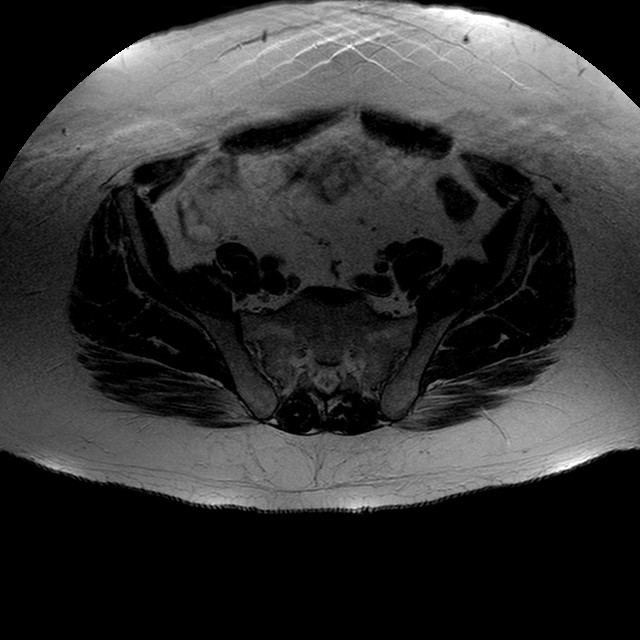

Esami: RMN BACINO

T2w TSE

Evidenti e simmetriche alterazioni osteofitosiche in regione coxo femorale con riduzione delle rime articolari. Degenerazione completa del cercine glenoideo. Non attuali segni di versamento articolare. Non segni di edema osseo che escludono attuale algodistrofia od osteonecrosi. Lieve e simmetrica riduzione del trofismo della muscolatura glutea.